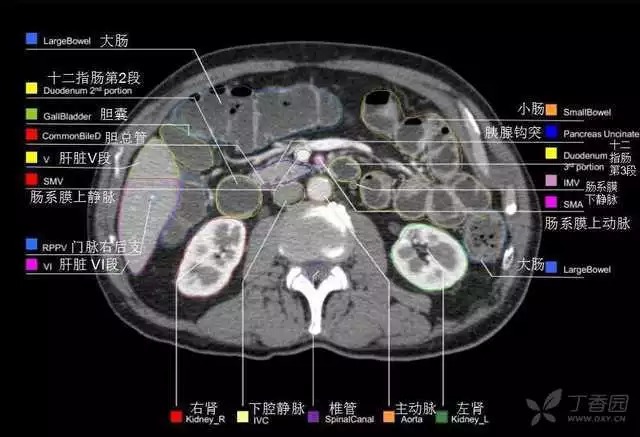

腹部肝脏高清CT断层的图谱

全腹部高清CT图谱,淋巴结彩色图谱,血管解剖图谱大汇总!